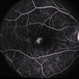

- neovascularization of iris (NVI), Iris, FA, iris fluorescein angiogram, Heidelburg Spectralis, smokestack

- Iris FA of a 74 year old male with neovascularization of the iris. Noted mild activity of NVI at the superior pupillary margin, recommending observation at time of visit.